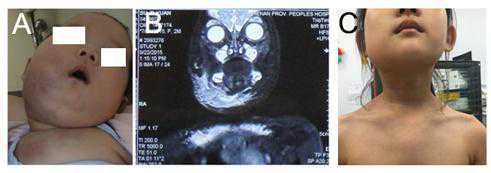

图:下颌、颈部巨大卡泼西样血管内皮瘤伴卡梅现象,患儿伴有明显的气道压迫症状。

卡梅现象(Kasabach–MerrittPhenomenon,KMP)是以巨大血管瘤伴血小板减少及消耗性凝血功能异常为特征的临床综合征,引起KMP的血管瘤主要是卡波西样血管内皮瘤(KHE)或丛状血管瘤(TA)。

卡波西样血管内皮瘤(KHE)最常见的表现为肿大、硬性、孤立性、紫癜性皮肤或软组织病变,好发于四肢浅表或深部软组织,也可发生在躯干、腹膜后、头颈部、纵隔、胸腺和脾等,可伴有局部多毛或多汗,瘤体局部有侵袭性,形态学特点与卡波西肉瘤类似。

3、经磁共振成像(MRI)等影像学检查证实;

4、经过病理活检证实。如果患儿病情严重,或有严重出血倾向,或肿瘤位于特殊部位而无法进行手术取得病理标本的,但影像学检查证实有巨大血管瘤存在,且伴血小板减少及凝血功能异常,也可临床诊断为KMP;